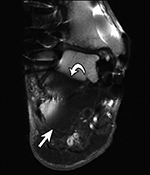

Failed fat-suppression. Coronal T2 fat-saturated image of the ankle with extensive susceptibility artifact due to distal fibular plate and screws shows failed marrow fat suppression involving the distal tibia and hindfoot with demarcation between successful (arrow) and failed suppression in the talus (curved arrow).